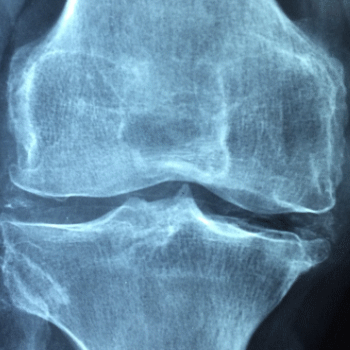

콘드로이친 효능 1. 관절 연골 보호 및 재생

콘드로이친은 관절의 연골을 보호하고 재생을 촉진하는 데 중요한 역할을 합니다. 연골은 관절에서 뼈와 뼈 사이를 부드럽게 움직이도록 돕는 쿠션 역할을 하는 조직입니다. 콘드로이친은 연골 세포를 보호하고, 외부 충격으로부터 연골을 보호하며, 세포외기질의 주요 성분으로서 연골의 구조와 기능을 유지합니다. 이를 통해 관절염 환자의 연골 손상을 줄이고, 새로운 연골 세포의 형성을 촉진하여 관절 건강을 개선합니다.

콘드로이친 효능 2. 관절염 증상 완화

콘드로이친은 골관절염과 같은 관절염 질환의 증상을 완화하는 데 효과적입니다. 연구에 따르면, 콘드로이친은 통증과 염증을 줄이고, 관절 기능을 개선하여 삶의 질을 높이는 데 도움을 줍니다. 관절염 환자는 종종 관절 부위의 통증과 뻣뻣함을 겪으며, 콘드로이친은 이러한 증상을 경감시켜 보다 자유로운 움직임을 가능하게 합니다.